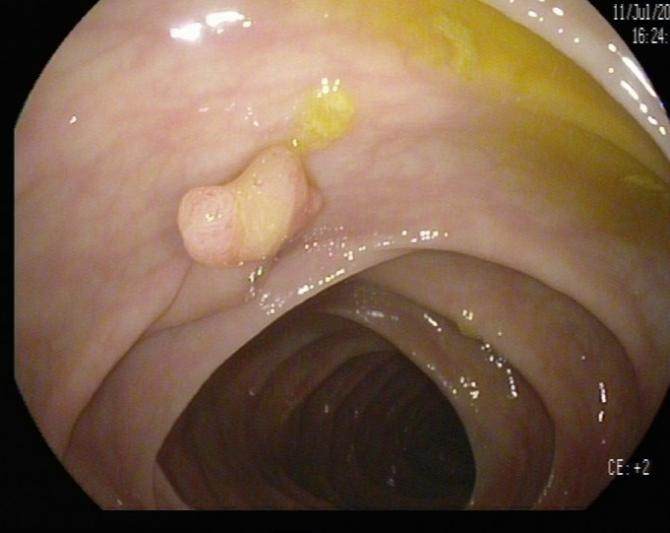

(2)陈先生(44岁,乙状结肠息肉,图2)

肠镜一照,息肉现形!形态各异的大肠息肉,离癌有多远?(图2)

图2

病理诊断:(乙状结肠)管状腺瘤,局灶癌变-黏膜内癌(腺癌),脉管未见癌栓,蒂未见累及。

解读:这是从腺瘤发展成癌的典型案例。“局灶癌变”指息肉中只有一小部分区域发生了真正的癌变。“黏膜内癌”指癌细胞仍局限于黏膜层内,尚未穿透黏膜肌层向更深层浸润。脉管无癌栓、蒂部未累及是非常积极的信号,表明癌细胞尚未通过血管/淋巴管扩散,也未侵犯息肉蒂部。此时完整切除息肉,很大可能达到根治效果。距离进展期癌:非常近,但尚属极早期,原位癌/粘膜内癌。